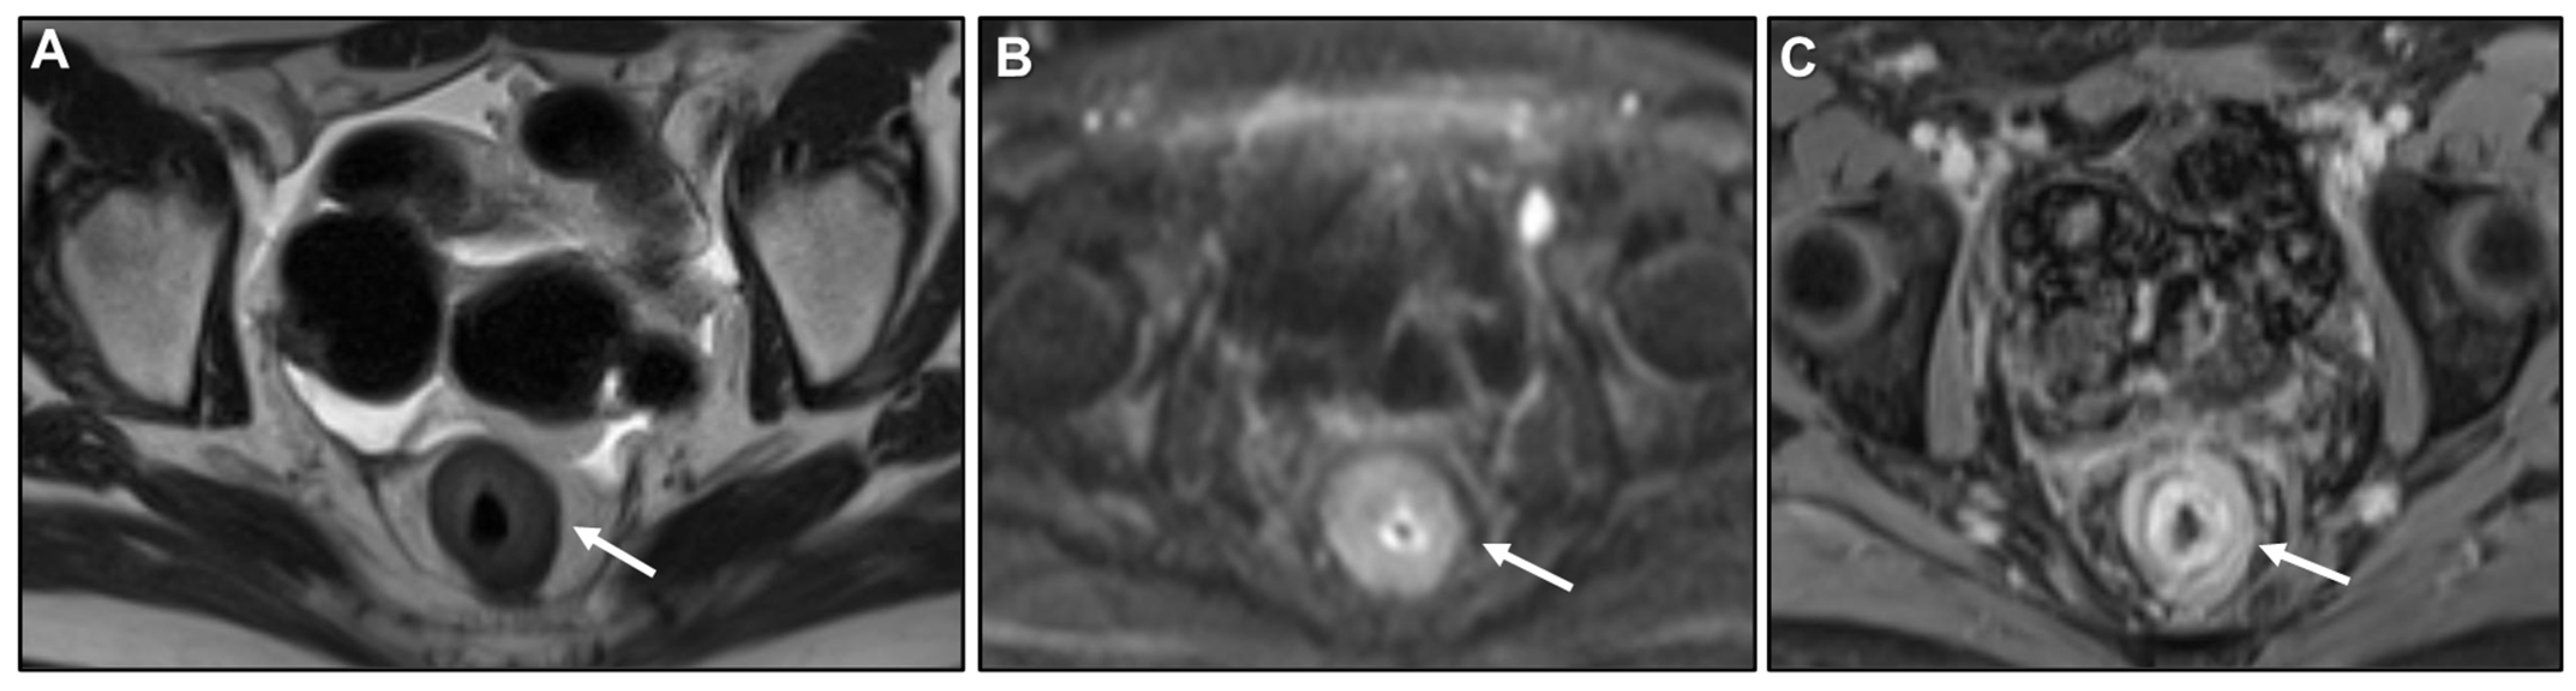

Concentric Ring Pattern

- Lau, L.C.; Wee, B.; Wang, S.; Thian, Y.L. Metastatic breast cancer to the rectum: A case report with emphasis on MRI features. Medicine 2017, 96, e6739. [Google Scholar] [CrossRef] [PubMed]

- Rudralingam, V.; Dobson, M.J.; Pitt, M.; Stewart, D.J.; Hearn, A.; Susnerwala, S. MR imaging of linitis plastica of the rectum. AJR Am. J. Roentgenol. 2003, 181, 428–430. [Google Scholar] [CrossRef] [PubMed]